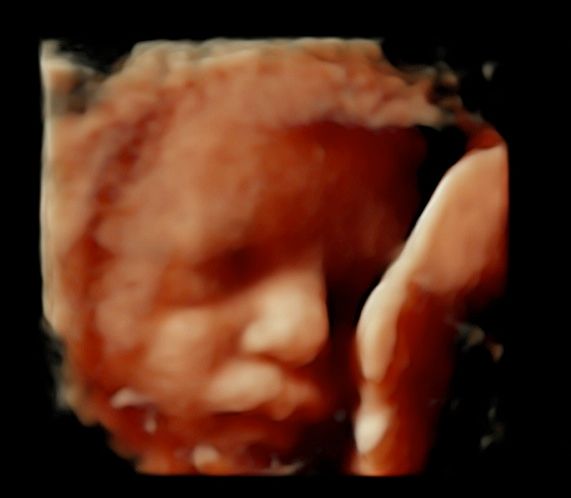

Foto e video

• Ecocardiografia fetale

• Ecografia morfologica